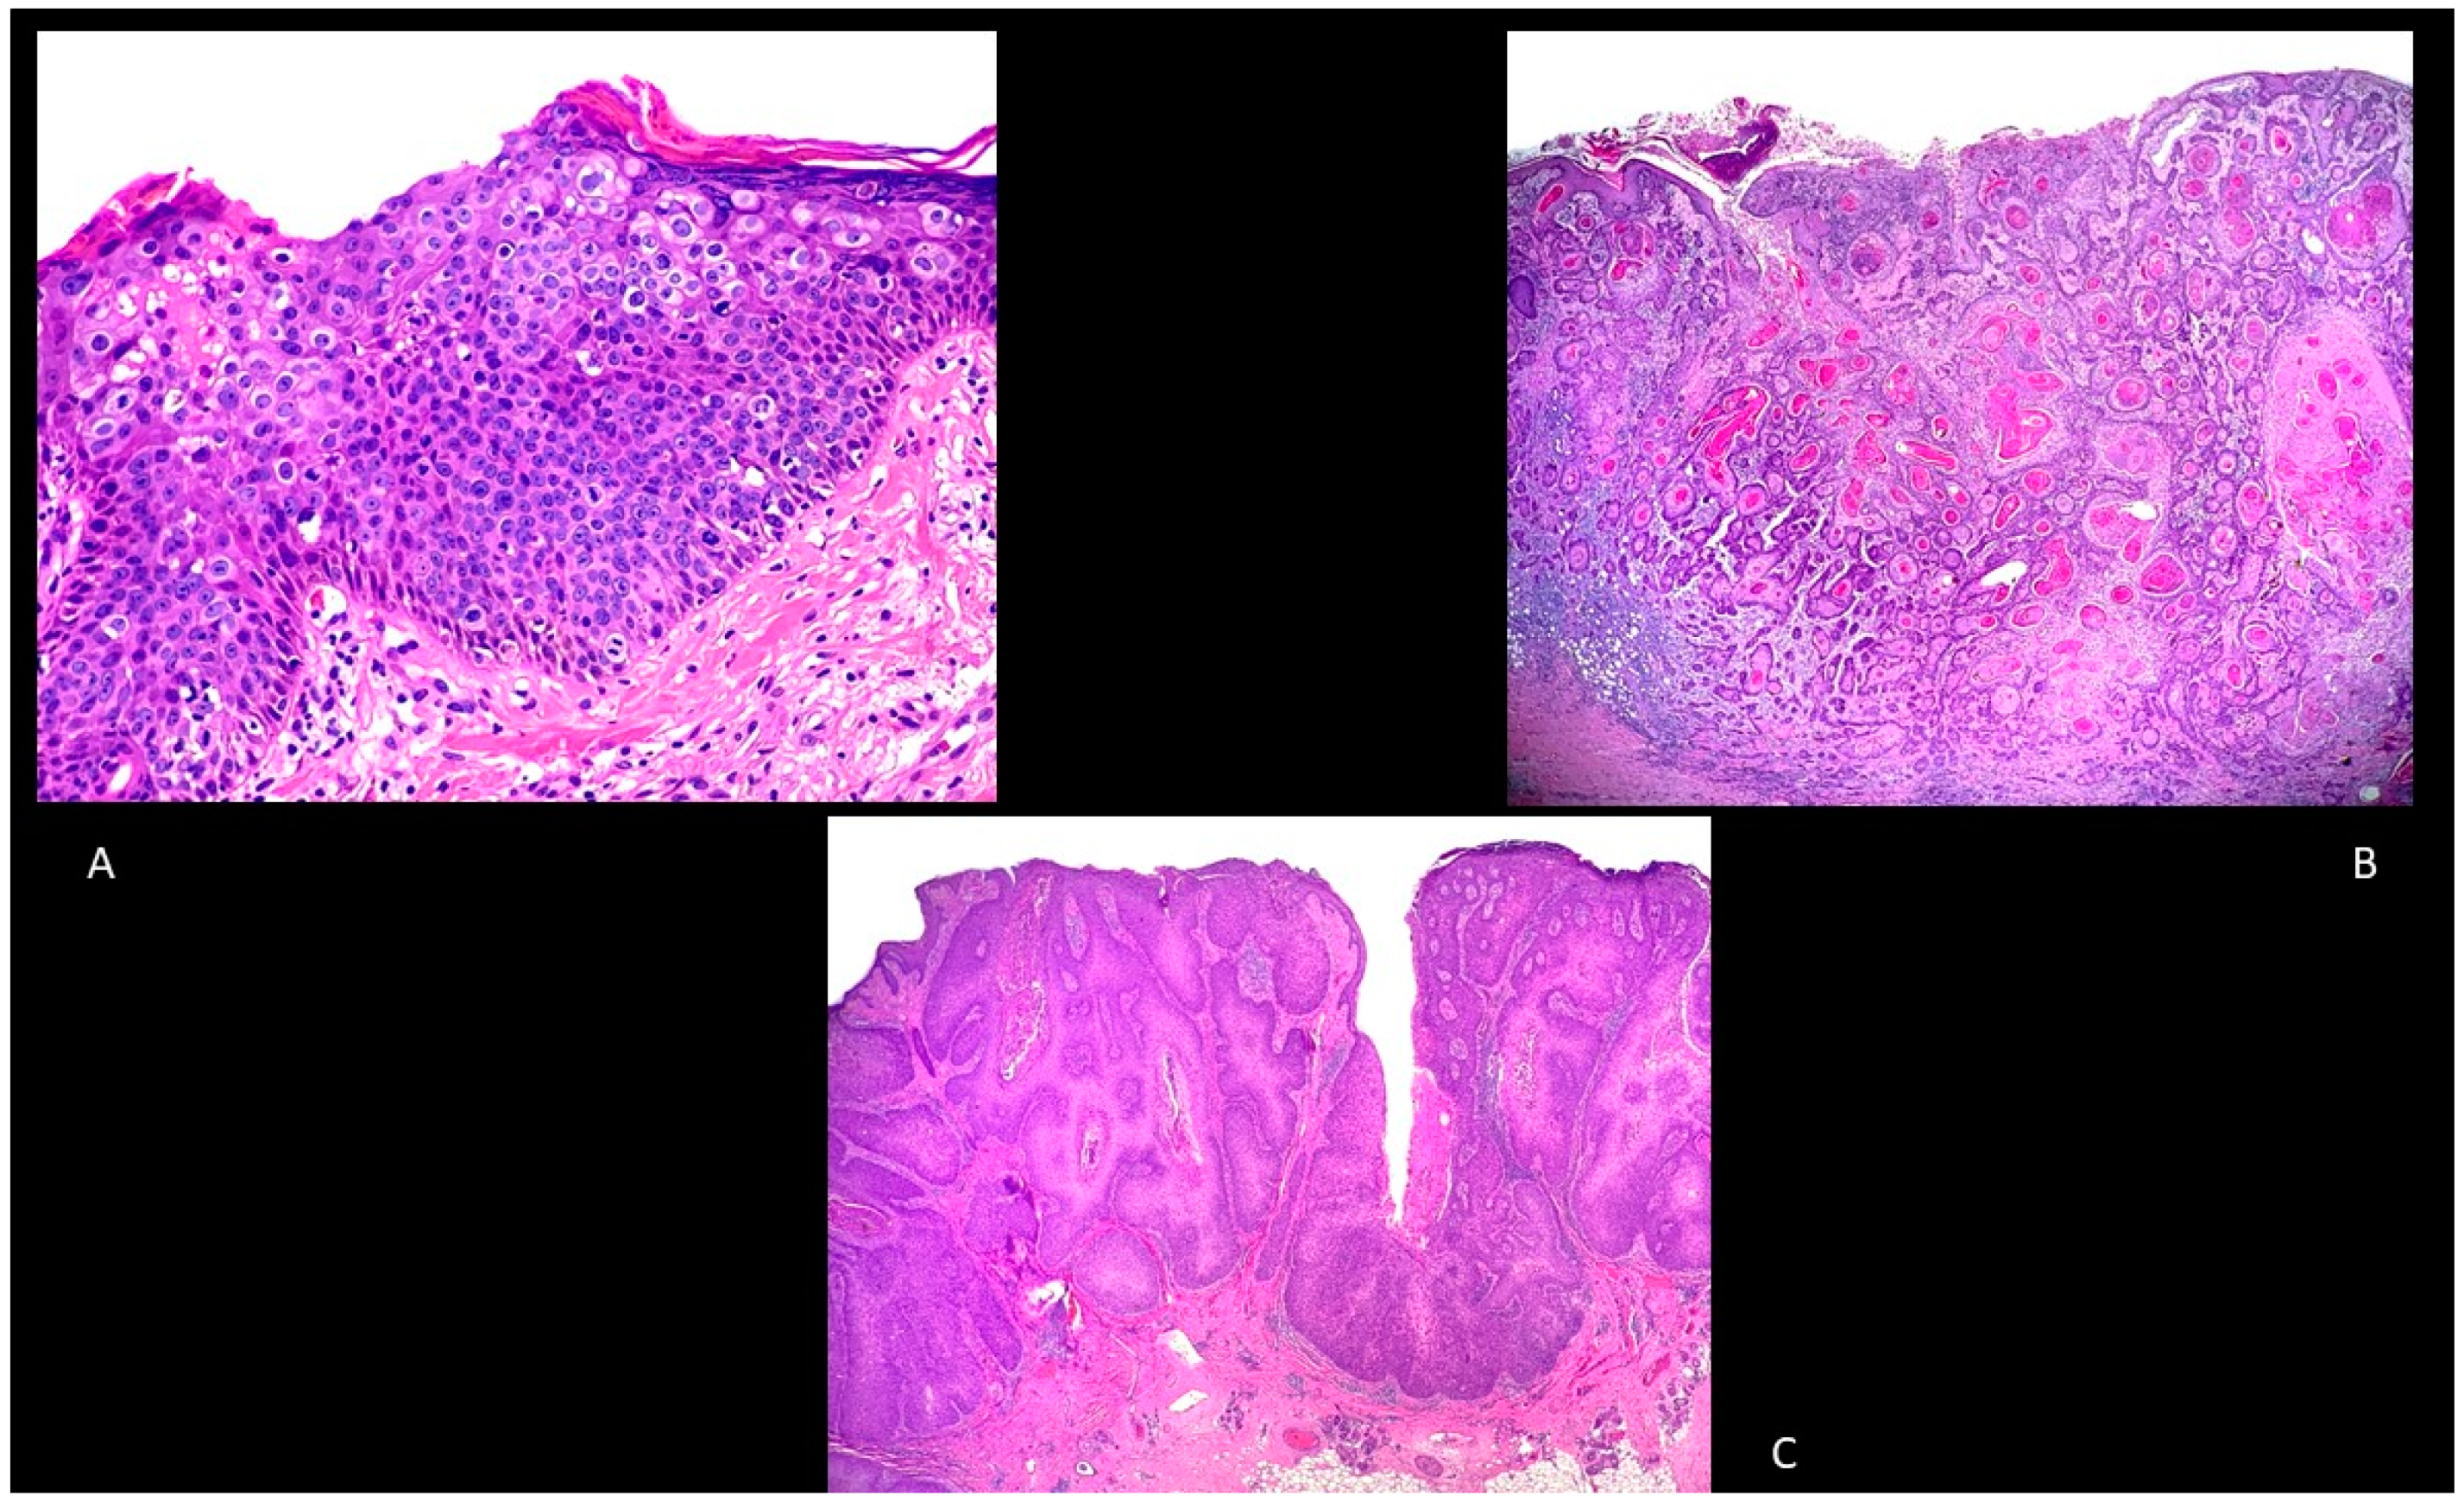

BD is an intraepidermal carcinoma with atypia of keratinocytes at all levels of the epidermis (in situ cSCC) [43]. The main histological features are parakeratosis, hyperkeratosis with an epidermis characterized by the presence of disordered maturation with atypical keratinocytes through all the epidermal layers, individual cell keratinization, pleomorphism of nuclei, atypical mitoses, and multinucleated tumor cells (Figure 2A). The basal layer is often not altered [43]. Keratinocytes can show pagetoid changes, while in other cases they show extensive clear cell changes. In the papillary dermis, a mixed inflammatory infiltrate characterized by lymphocytes and plasma cells can be often detected [43]. To exclude a melanoma, S100, Human Melanoma Black (HMB)-45 and Melan-A, and cytokeratin stains are usually employed [43].

Figure 2.

(A): Bowen’s disease. Hematoxylin and Eosin, 100× (B): Well-differentiated, invasive squamous cell carcinoma, hematoxylin and eosin, 20×. (C): Verrucous squamous cell carcinoma, hematoxylin and eosin, 20×.

Invasive cSCC is an epithelial malignancy characterized by atypical keratinocytes with a locally destructive growth and increased risk of metastatization. Histologically, it is mainly characterized by atypical and dyskeratotic keratinocytes with hyperchromatic and pleomorphic nuclei with mitoses (Figure 2B). Well-differentiated cSCCs typically have horn pearls and single cell keratinization, while poorly differentiated cSCCs usually show a lack of keratinization and many atypical mitoses. A mixed inflammatory infiltrate is usually present. Since the grade of differentiation is an important predictor, Broder’s staging is used to assess this parameter: grade I includes tumors composed of <25% undifferentiated cells, grade II lesions with <50% undifferentiated cells, grade III lesions with <75% undifferentiated cells, and grade IV lesions with >75% undifferentiated cells [40].

Verrucous cSCC (also known in genital areas as Buschke–Löwenstein tumor) is characterized by exophytic squamous proliferation with marked papillomatosis and low atypia, the presence of koilocyte-like changes, and a central collection of neutrophils (Figure 2C).

Adenosquamous cSCC is another type of cSCC characterized by a mixed glandular and squamous differentiation with an aggressive behavior (Figure 3A) [40].

Figure 3.

(A): Adenosquamous squamous cell carcinoma. Hematoxylin and eosin, 200×. (B): Perineural squamous cell carcinoma. Hematoxylin and eosin, 100×. (C): Papillary squamous cell carcinoma. Hematoxylin and eosin, 40×.